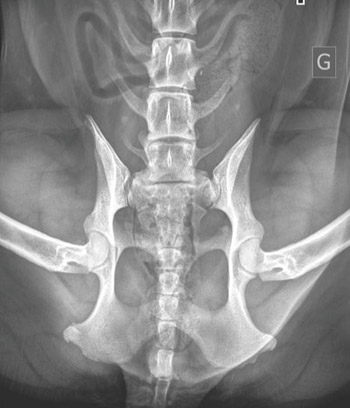

Les Vertèbres Lombo-Sacrées (VTL)

Il est désormais possible de demander le dépistage des vertèbres de transition lombo-sacrées (VTL).

DE QUOI S'AGIT-IL ?

Cette anomalie concerne la région terminale de la colonne vertébrale, entre les vertèbres lombaires et le sacrum. Elle peut entraîner des troubles locomoteurs ou des complications articulaires.

POURQUOI DÉPISTER ?

Les VTL sont des anomalies congénitales et héréditaires. Le dépistage permet de limiter leur diffusion dans la race.

COMMENT DÉPISTER ?

Le dépistage se fait par radiographie à partir de 12 mois, dans la même position que la radio de dépistage des hanches.

La classification distingue les VTL0, VTL1, VTL2 et VTL3. Contrairement aux dysplasies, ces catégories correspondent à des types d'anomalies et non à un degré de gravité.

Il est recommandé de favoriser les reproducteurs VTL0.

COMMENT FAIRE LA DEMANDE ?

Le dossier est à constituer dans les mêmes conditions que pour les dysplasies HD et ED. Les résultats sont transmis à la SCC pour enregistrement.

NOTA BENE : Les propriétaires ayant réalisé des radios en 2023 peuvent contacter la commission Dépistage pour étudier la faisabilité du dépistage VTL avec le même cliché.